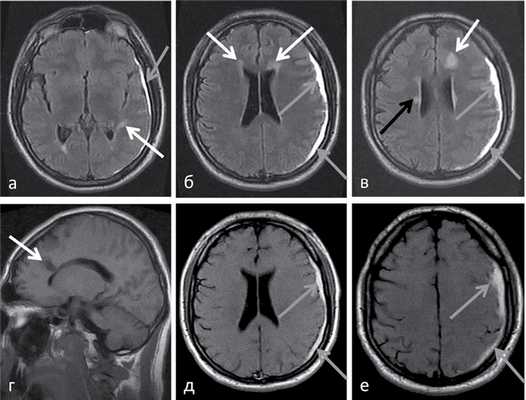

(а) МРТ-исследование в динамике, FLAIR, аксиальный срез: у этой же пациентки в возрасте 3,5 лет в левом таламусе определятся новая зона слабого повышения интенсивности сигнала. Кроме того, в коре/субкортикальном белом веществе затылочных долей визуализируется новая протяженная зона гиперинтенсивного сигнала и отека.

(б) МРТ, ДВИ, аксиальный срез: в пораженных зонах визуализируется снижение интенсивности сигнала, что указывает на подострый их характер. По данным протонной МР-спектроскопии (не представлены) было выявлено наличие лактата, что часто наблюдается в подострой стадии.

(а) MPT, Т2-ВИ, аксиальный срез: у девочки 12 лет с давним анамнезом MELAS определяется распространенная потеря объема коры и субкортикального белого вещества больших полушарий в сочетании с повышением интенсив нсоти сигнала от перитритонального белого вещества и субкортикального белого вещества/коры теменно-затылочных областей.

(б) МРТ, ДВИ, аксиальный срез: у этого же ребенка отмечается ограничение диффузии в области полюса левой затылочный доли, что указывает на острое поражение на фоне хронических изменений.

(а) MPT, ДВИ, аксиальный срез: у девочки возрастом 22 дня с микроцефалией молочнокислым ацидозом отмечается нормальная картина; зон ограничения диффузии не выявляется.

(б) Протонная МР-спектроскопия, время эхо 144 мс с зоной интереса в базальных ганглиях: у этой же пациентки подтверждается наличие дублета лактата на 1,3 ppm. Обратите внимание, что пик лактата инвертируется при времени эхо 135-144 мс. Протонная МР-спектроскопия с использованием данного времени эхо может помочь отличить лактат от липидов.